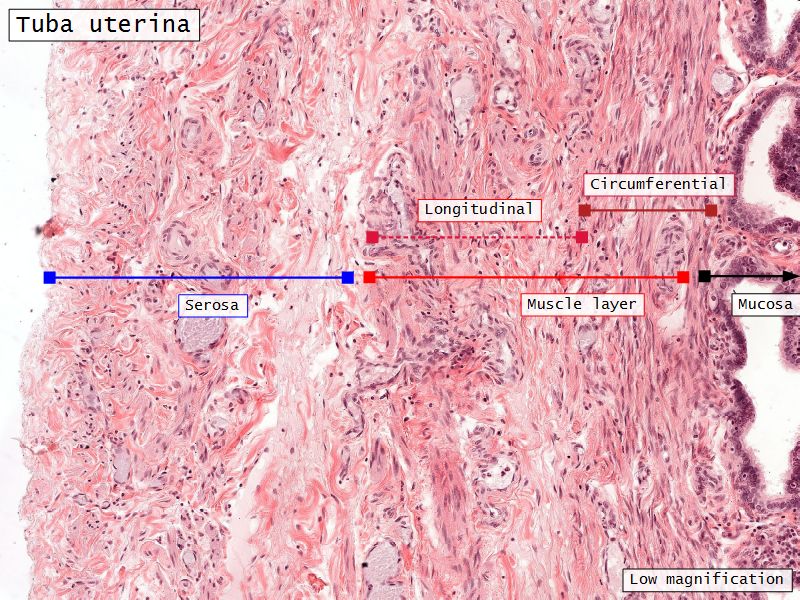

Three layers

- Mucosa

- Muscular layer

- Serosa

Muscular layer

- Ill-defined

- Inner circular

- Outer longitudinal

- Play role in moving zygote towards uterus

Serosa

- Simple squamous epithelium

- Contains

- Blood vessels

- Lymphatics

- Nerves